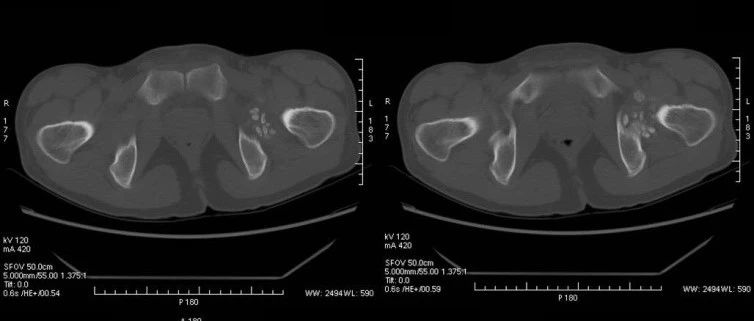

医学影像  yxyx-app  医学影像APP,打造伴随医生快速成长的影像学习社区。与影像园(Xctmr.com)一起提供最全面的影像案例库、基础(解剖、病理、影像诊断)知识、影像技术及考题等,为医生提供最佳的医学影像参考。【所属科室】骨科【基本资料】患者,男,30岁【主诉】左髋部酸胀半年【影像图片】【讨论问题】如何诊断?【医学影像APP用户讨论】评论:左髋关节周围见多发类圆形结节影,边界清,呈环状高密度,中央密度低。考虑滑膜骨软骨瘤病。...

音频课程2022 · Audio Course文  捷湖南省人民医院儿童骨科点击收听✦学习笔记儿童髋关节疼痛是临床非常常见的症状,导致儿童髋关节疼痛的常见疾病包括髋关节暂时性滑膜炎、化脓性髋关节炎、 Perthes病等,通常结合患儿的病史,疼痛的特点,体征以及X线、B超等辅助检查可以明确诊断。滑膜软骨瘤病是一类关节滑膜自限性增生,形成滑膜内软骨结节和关节游离体的慢性关节疾病,是一种良性病变,可发生于任何滑膜关节,滑膜软骨瘤病多见于...

音频课程2022 · Audio Course陈飞雁复旦大学附属华山医院骨科点击收听✦学习笔记滑膜软骨瘤病(Synovial chondromatosis SC)是种相对罕见的关节滑膜或滑膜囊、腱鞘发生异常增殖的疾病。最早称为Reichel’s综合征,1958年Jaffe将本病命名为“滑膜软骨瘤病”。本病最常发生在膝关节,其次可影响髋关节、肘关节、踝关节、颞下颌关节和肩关节等部位。以滑膜形成软骨结节为特征,可带蒂生长,亦可能脱落到关节腔形成游离体(关节鼠),后期可发生钙化或骨化。...